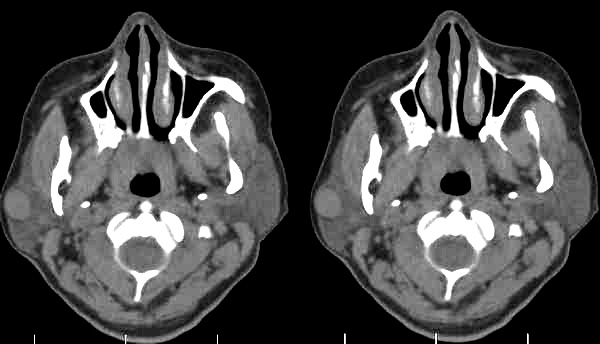

标题: CT2109:右腮腺区肿物

女35岁,右腮腺区肿物一年余

肿块边界清楚锐利,考虑腮腺混合瘤,建议增强。

病史长,病灶光滑锐利、密度均匀,未见坏死,右侧腮腺浅叶的混合瘤首先考虑

右侧腮腺浅叶圆形稍高密度影,边缘光整,考虑腮腺囊腺淋巴瘤。